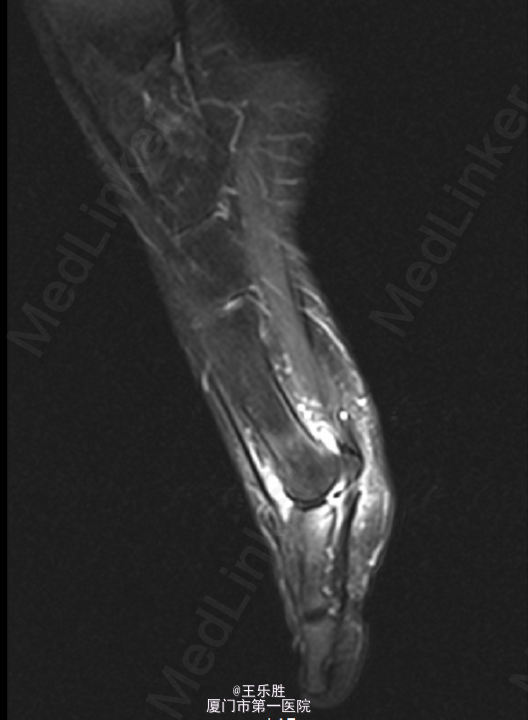

患者,女,58岁,因“右足跖趾关节酸痛半年”入院。

右足第一跖趾关节前侧可见红肿,关节处无明显压痛,关节活动尚可,足背动脉可及,足趾伸屈正常。远端血循良好,感觉正常。我院 MRI示右足第1跖趾关节积液,滑膜炎考虑。

初步诊断:右足第一跖趾关节滑膜炎.行“右第1跖趾关节滑膜切除+关节清理+骨赘切除术 ”.